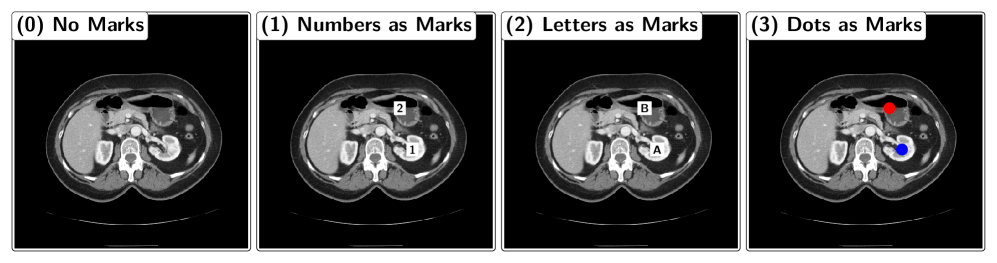

We introduce the MIRP Benchmark dataset to systematically evaluate VLMs’ ability to identify relative positions in medical images. The dataset consists of abdominal CT slices, each paired with a question about the relative position of two anatomical structures, following a standardized template: “Is the structure1 above/below/to the left of/to the right of the structure2?”. The slices are randomly rotated and flipped to ensure that the model must derive relative positions from the image rather than relying on anatomical priors to produce a correct answer. The MIRP dataset is balanced, with an equal distribution of yes and no answers to questions. The two anatomical structures referenced in the question are optionally highlighted with visual markers. Three marker types are evaluated: (1) black numbers in a white box, (2) black letters in a white box, and (3) a red and a blue dot (see Figure 2). The following sections describe the dataset generation process and the VLM evaluation pipeline. While these sections are not required to understand the experiments and results, they provide additional context for our study.

Figure 2: Different visual markers. Note: The real marks are smaller as shown here.